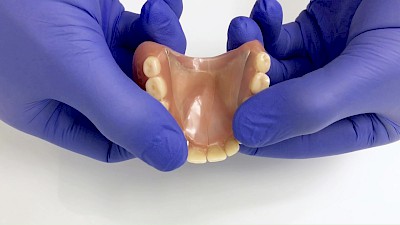

Schlechter Halt & schlechte Passung

Immer wieder kommt es vor, dass Zahnprothesen schlecht passen und/oder schlecht halten. Eine schlechte Prothesenpassung zeigt sich daran, dass die Prothese stark "schaukelt", wenn man auf die Zahnreihen drückt. In erster Linie ist dies auf den Knochenschwund, die sogenannte Atrophie, zurückzuführen. Knochenschwund ist individuell sehr unterschiedlich ausgeprägt. Genetische Veranlagung aber auch intensives Tragen der Zahnprothese sowie ständiges Knirschen und Pressen können Einflussfaktoren sein.

Ein übermäßiger Bedarf an Haftmitteln wie zum Beispiel Haftcreme, lässt ebenfalls auf eine schlechte Passung schließen. Halten Prothesen auch mit normaler Menge Haftcreme nicht, sollte ein Zahnarzt gerufen werden.